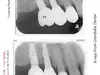

Dr. Rebecca Vanderbaan & Dr. Larissa Bishop The Past President Of The WMDDS Placed A Dental Crown Tooth #3 Backwards And Wrecked My Restoration. A Bridge became loose, A veneer chipped, A crown fell off, another crown became loose, 8 teeth are not touching each other and I have bone loss on several new implants likely caused from this.

How did a implant supported crown get placed 180 degrees backwards then get missed then several adjustments to the adjacent teeth were made on four different separate occasions until there was no bite on 8 teeth. Permanent adjustments were made to teeth #5, #6, #7, #26, #27 and #28 all based on a crown tooth number 3 being placed backwards and then let me go with a non-functioning bite.

The WMDDS should be looking hard at Photo #120 and look close at tooth #3 then compare it to the model the way the tooth was supposta be placed and you will see tooth #3 was placed 180 degrees backwards and not known for a whole year biting my tongue and cheek everyday over 300 times and sometimes to the point of bleeding and I told the dentist my tooth #3 is biting my tongue and check every single day but everyone ignored it and let me keep biting myself. Photo #120 is the photo that the dental association was weirdly missing. The WMDDS should go back and actually look at this case and see how the clinical exam was unfair, biased and no x-rays or bitechecks were even taken during there clinical exam.